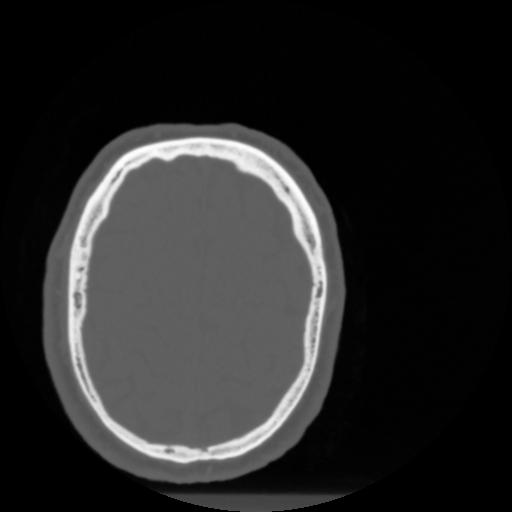

4 CEREBRO,,Vol,0.5,CEREBRO,,